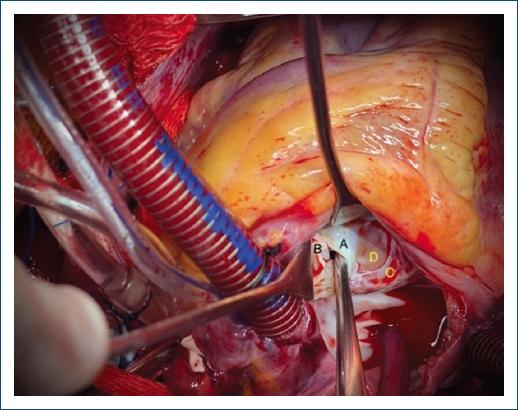

El síndrome de Laubry-Pezzi es una malformación cardiaca no sindromática y poco frecuente, caracterizada por una comunicación interventricular (CIV) e insuficiencia aórtica, las cuales producen prolapso de la valva coronariana derecha y menos frecuente de la valva no coronariana1. Presentamos el caso de un paciente de 14 años con presencia de soplo cardiaco en etapa preescolar diagnosticándose una comunicación interventricular subaórtica con prolapso valvular aórtico e insuficiencia aórtica moderada (Fig. 1). En las valoraciones subsecuentes presenta disminución en la clase funcional y ecocardiográficamente incremento de la insuficiencia aórtica, por lo que se decide cierre del defecto. Durante el procedimiento quirúrgico se realiza prueba hidráulica identificando prolapso y perforación de valva no coronariana de aproximadamente 5 x 8 mm de diámetro (Fig. 2), lo cual es sumamente infrecuente. La asociación de CIV infundibular con prolapso e insuficiencia aórtica es rara, con una incidencia aproximada del 5 al 10%, siendo el prolapso progresivo y con presencia de defectos pequeños; se ha observado que tienden a evolucionar con mayor rapidez la insuficiencia aórtica2. Al ser una patología poco frecuente, la decisión de intervención quirúrgica es un tema controvertido, sin embargo, algunos autores refieren que debe considerarse al igual que cualquier defecto interventricular, es decir, se debe realizar el cierre quirúrgico cuando se observe insuficiencia aórtica independientemente de la repercusión hemodinámica de la cardiopatía, ya que el desarrollo de esta puede complicar el pronóstico y la supervivencia del paciente2.